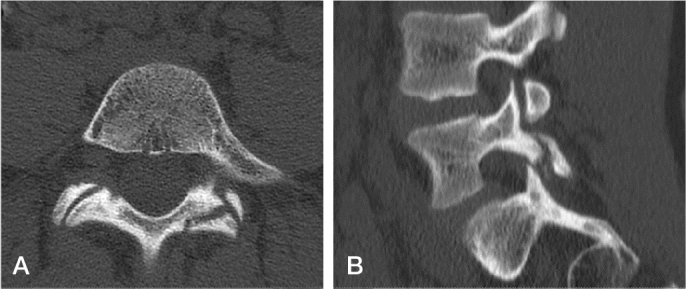

峡部裂被定义为腰椎关节间部缺损或伸长,单侧或双侧均可。患有双侧峡部裂的成长期儿童可能会出现椎体滑脱,即受影响的椎体向前滑动。峡部裂的病因被认为是由于与遗传易感性相关的重复性负荷导致的应力性骨折。腰椎磁共振成像(MRI)显示在实际骨折线形成之前信号强度增加。在轻度椎体滑脱中,三分之二的急性小儿椎体滑脱患儿会在早期活动受限的情况下进行骨愈合。与骨不愈合的患者相比,实现骨愈合的患者的健康相关生活质量得到改善,其中四分之一的患者会进一步发生脊柱滑脱。对于高度椎体滑脱的患者(定义为受影响椎体向前滑动超过50%),建议进行脊柱融合术以防止进一步进展。

Spondylolysis is defined as a defect or elongation in the pars interarticularis of the lumbar spine, either unilateral or bilateral. Growing children with bilateral spondylolysis may develop spondylolisthesis, i.e., forward slipping of the affected vertebra. The etiology of spondylolysis is regarded as a stress fracture due to repetitive loading associated with a genetic predisposition. Lumbar magnetic resonance imaging (MRI) shows an increased signal intensity before an actual fracture line develops. In low grade spondylolisthesis, two-thirds of children with acute pediatric spondylolysis will undergo bony union with early activity restriction. Health-related quality of life is improved in patients achieving bony union as compared with patients having non-union, of which one-fourth will additionally develop spondylolisthesis. In patients with high-grade spondylolisthesis, defined as a more than 50% forward slippage of the affected vertebra, spinal fusion is recommended to prevent further progression.